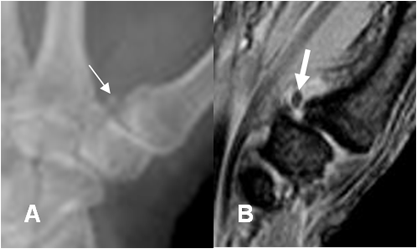

Fig 59 B. Luxofractura de Bennet.

A: Rx AP y B: Rx oblicua. Subluxación de la articulación carpometacarpiana del pulgar y fractura en la base del metacarpiano, por luxofractura de Bennet.

Fig 59 C. Luxofractura de Bennet.

A: Rx oblicua. Luxofractura de Bennet, con pequeño fragmento suelto medial.

B: RM oblicua en STIR. Escasa cantidad de líquido articular y subluxación carpometacarpiana. Se identifica fragmento libre. (Flecha gruesa).